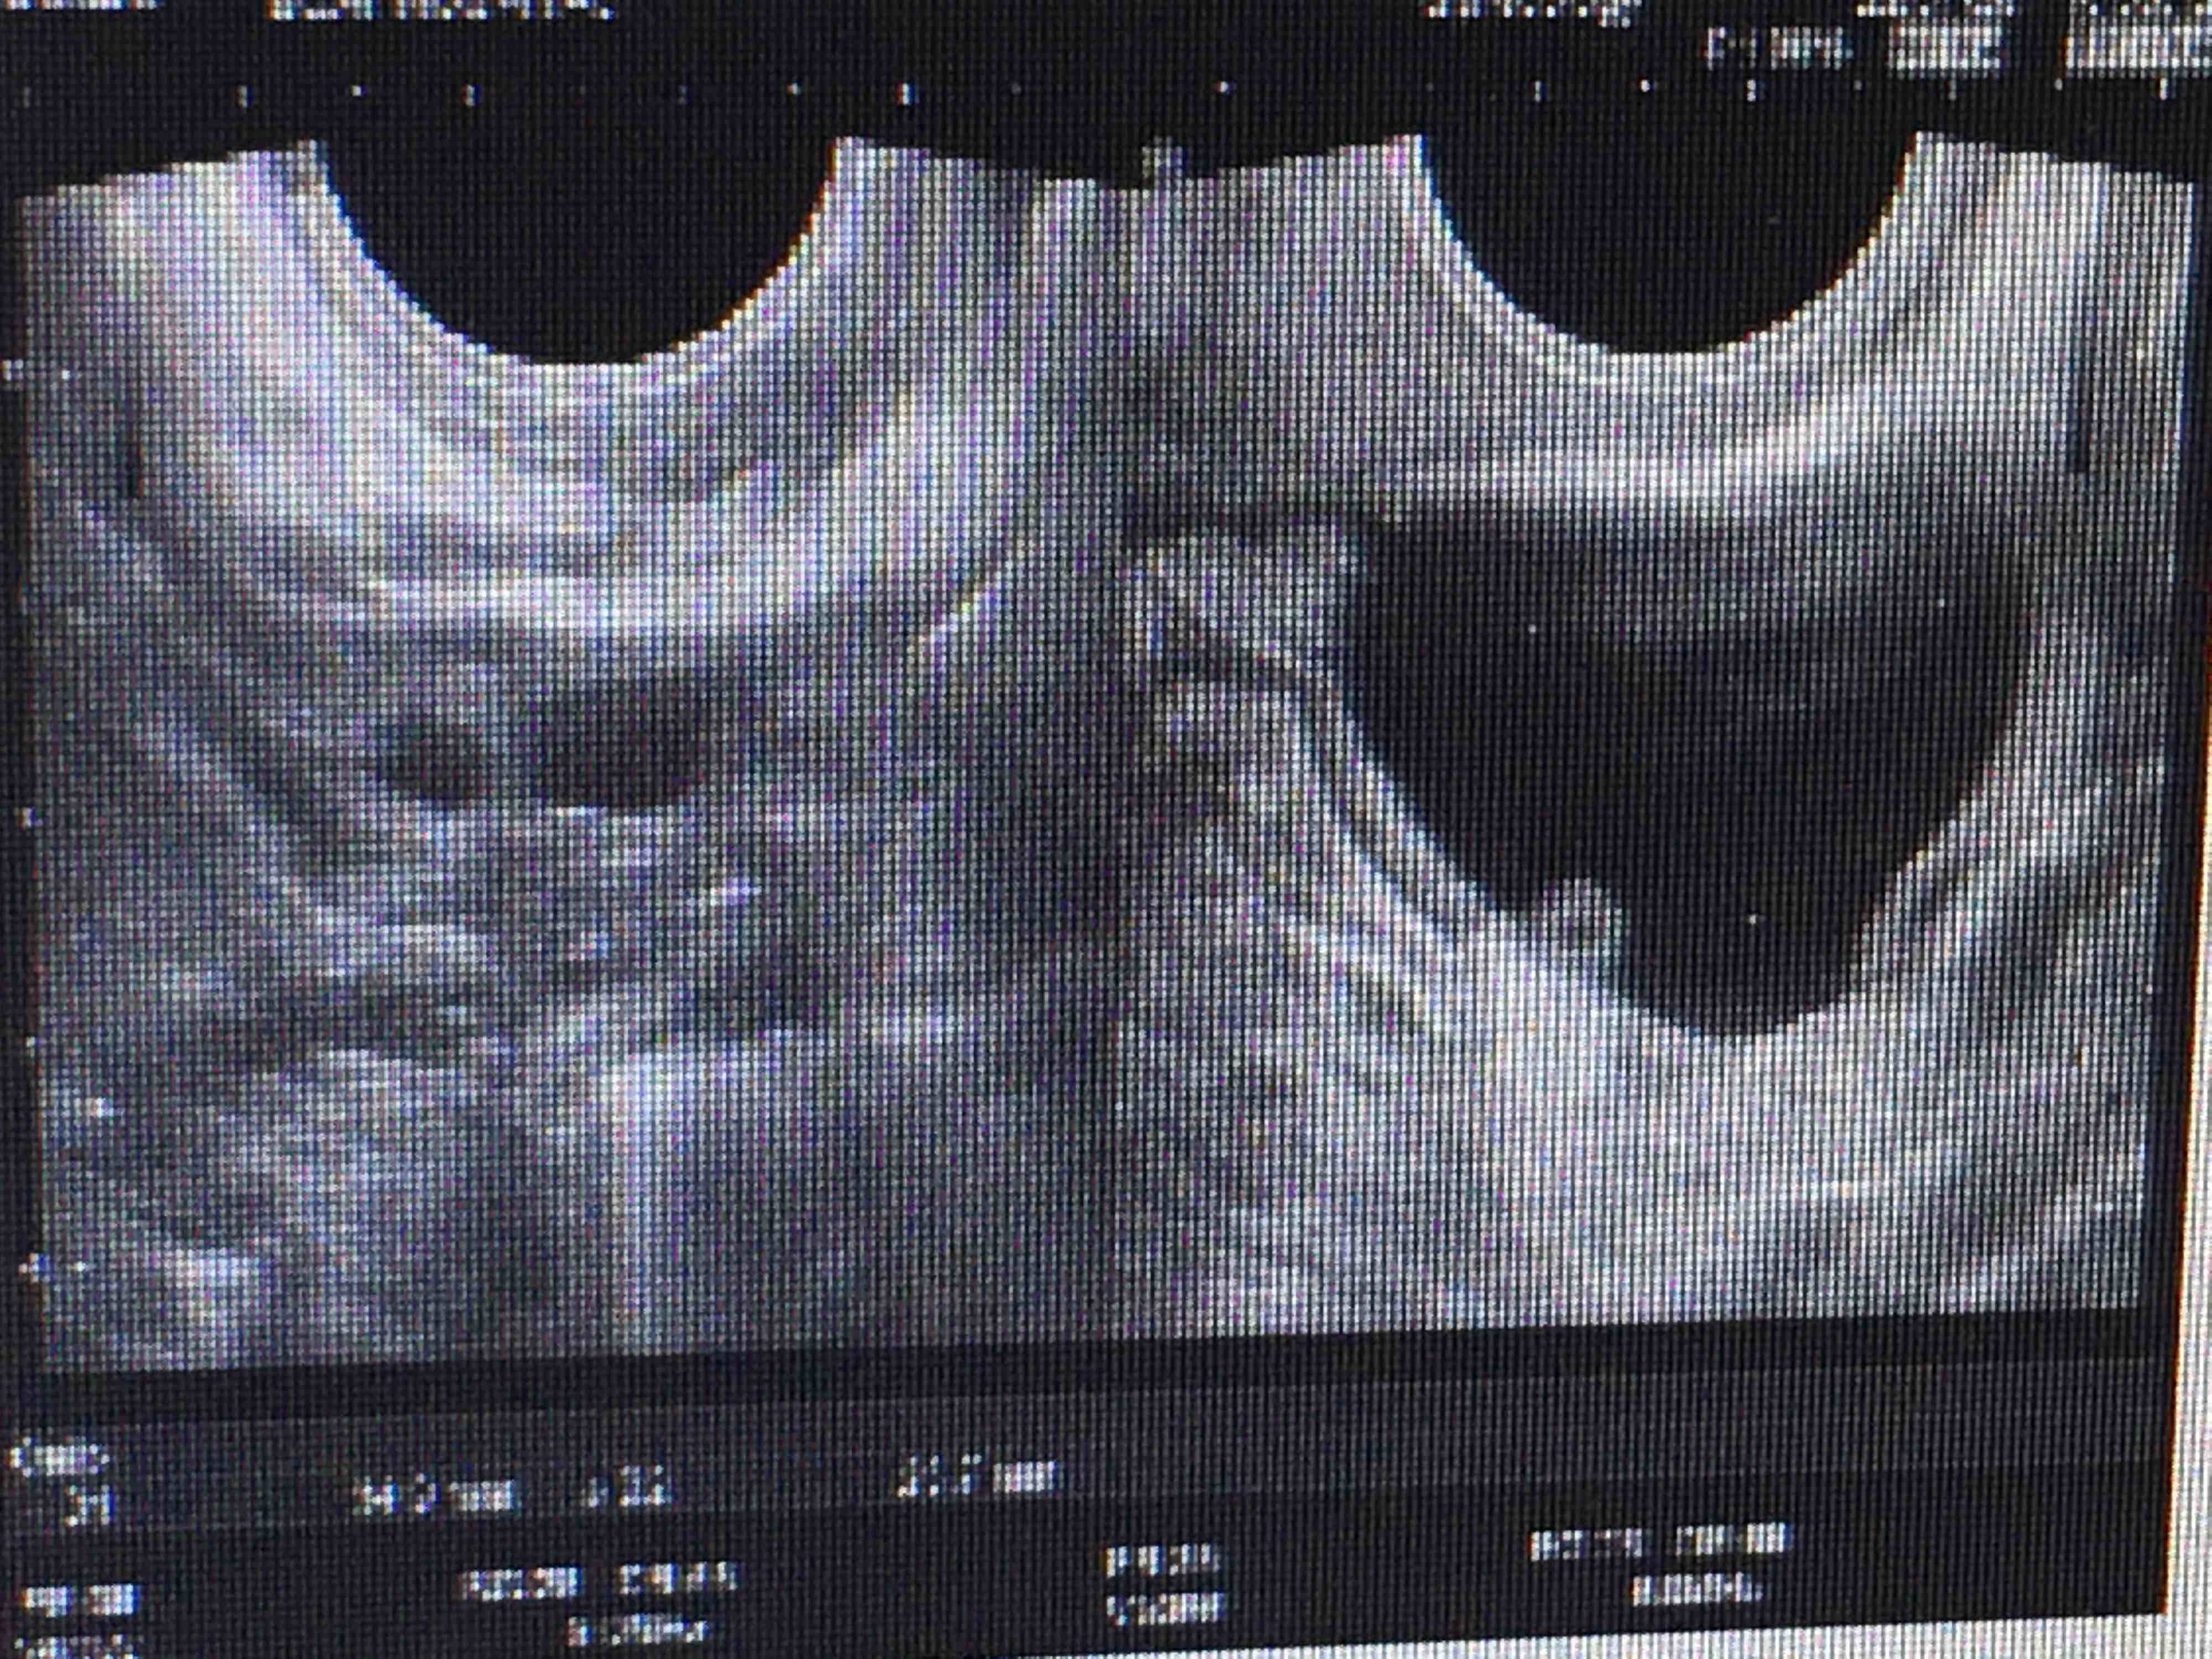

很多备孕妈妈都有过这样的经历:自己在家测了排卵试纸由弱阳性变强阳性,去医院B超检查,也能看到卵泡由小变大,长到18–22mm了,第二天再去检查,卵泡没有破,反而越来越大了,隔几天去查,这个卵泡仍然存在,或者B超提示卵泡形态不规则或者张力不好了,这是为什么呢?

卵泡成熟了不排卵或者萎缩塌陷,叫卵泡黄素化,是排卵障碍的一种表现,见于自然排卵周期,也见于促排卵周期,未破裂的卵泡多数在月经来潮前消失,也有的是在月经干净后消失,还有一些持续长大超过30mm以上,称为黄体囊肿,属于功能性囊肿,经过1到2个月经周期自然消退,一般不需要治疗。